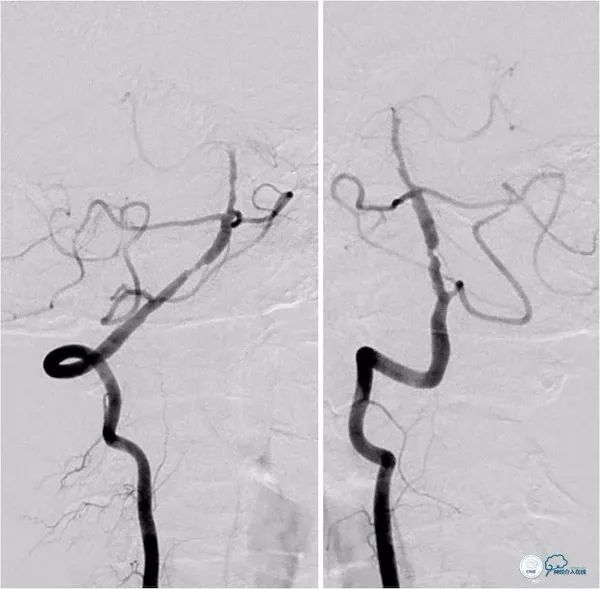

治疗过程简述:全麻下右股动脉入路, 6F Guiding导引导管至右椎动脉V2段远端,术中造影示右椎动脉V4段重度狭窄,基底动脉中段中重度狭窄(图11)。

将Transend微导丝(0.014″,300cm)通过狭窄,放置在左小脑上动脉,沿微导丝送入Gateway球囊(2.0mm×15.0mm)于狭窄处预扩张(图12)。

撤出球囊导管,沿Transend微导丝送入Wingspan自膨式支架(3.0 mm×20.0mm),释放后造影示支架贴壁良好,前向血流TICI 3级(图13,14)。

图13

图14

本例系右椎动脉V4段及基底动脉串联狭窄,但基底动脉狭窄远端侧支代偿,未予以同期处理;右椎动脉V4段狭窄系偏心分布,毗邻穿支且斑块波及范围较广,故球囊预扩张后放置了一稍长长度的Wingspan支架。